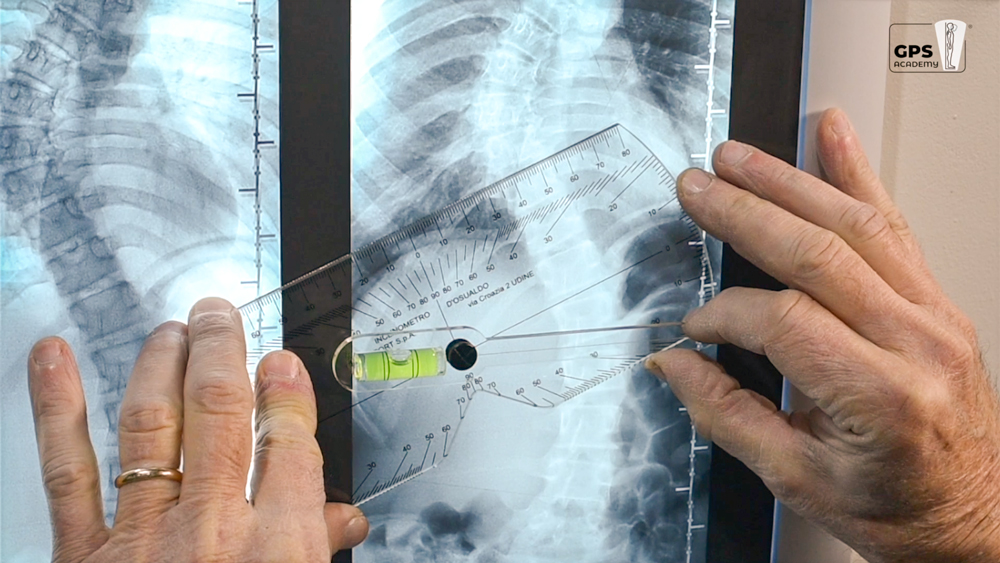

L’inclinometro di D’Osualdo è uno strumento originale che riunisce due importanti funzioni: la misurazione del gibbo (angolo di rotazione del tronco in anteroflessione) nel paziente affetto da scoliosi e la misurazione dell’angolo di Cobb sulle radiografie; in questo caso può essere utilizzato sia nelle curve sul piano frontale (scoliosi) sia nelle curve sul piano sagittale (cifosi e lordosi).

Nella misurazione delle radiografie il bordo dello strumento viene accostato al bordo della vertebra limite superiore della curva, l’asta viene quindi ruotata fino a metterla in bolla; il grado di inclinazione viene letto sulla scala goniometrica; l’operazione viene quindi ripetuta per la vertebra limite inferiore. L’angolo di Cobb è dato dalla somma degli angoli di inclinazione delle due vertebre limite.

L’inclinometro è utile anche per la precisa identificazione sulla radiografia delle vertebre limite che sono appunto le più inclinate.

L’inclinometro è composto da un elemento quasi-rettangolare di plexiglas, recante una scala goniometrica, al cui centro è fissata una piccola asta libera di ruotare attorno allo stesso centro e recante una bolla; l’estremità libera dell’asta reca l’indice di lettura per la scala goniometrica; il lato più lungo del rettangolo presenta una rientranza per renderne più agevole l’applicazione sul paziente (in caso di spinose sporgenti).